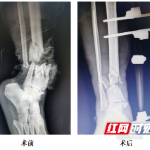

入院后约20分钟,刘亮被送入了手术间。骨科手术团队随即对患肢进行彻底清创,并用外固定支架固定骨折;随后在显微镜下,先后对胫前、胫后动脉及伴行的4根静脉、肌腱以及神经进行精准吻合。

经过9个小时的努力,骨科手术团队将其右小腿成功接回。